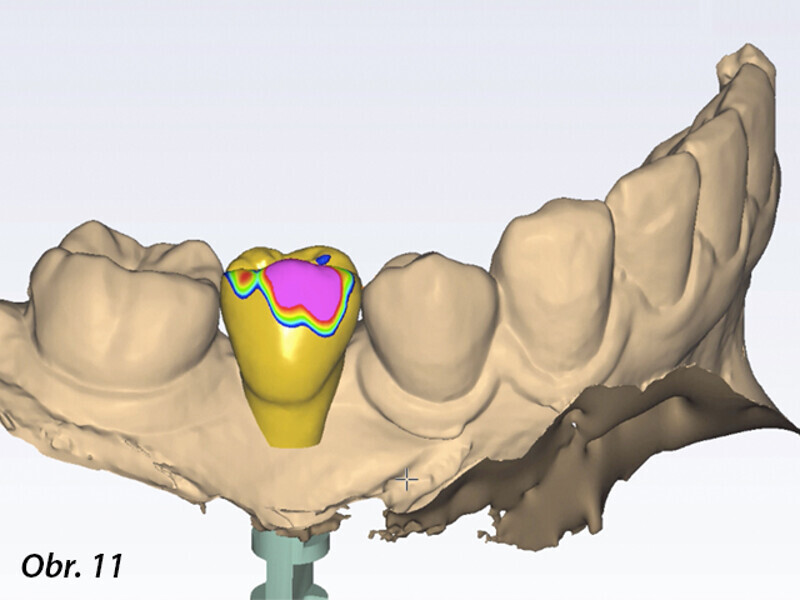

Řízená implantologie za použití řešení Planmeca all-in-one